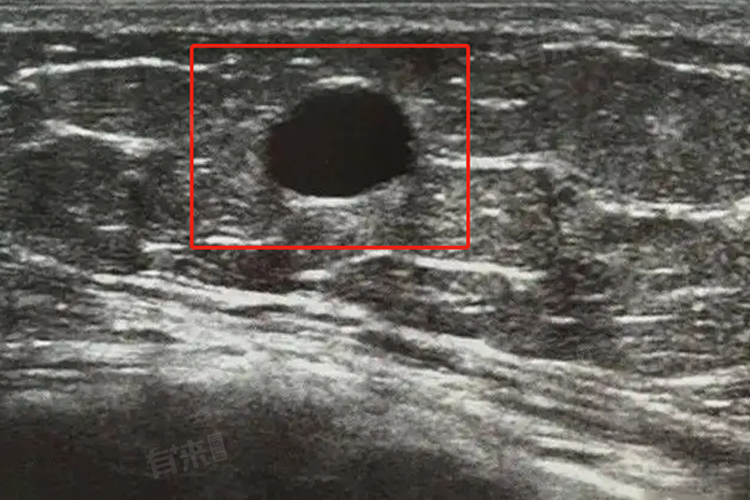

双侧乳腺囊性结节BI-RADS2类,是乳腺影像学检查中常见的一种诊断结果,它表示在患者的双侧乳腺内存在囊性病变,即结节内部含有液体。

- BI-RADS是乳腺影像报告与数据系统的缩写,该系统将乳腺超声检查结果分为6个等级,以评估乳腺病变的恶性可能性。其中,第2级表示病变为良性增生,不属于恶性病变。因此,双侧乳腺囊性结节BI-RADS2类意味着超声检查发现的结节很可能是良性的,恶性可能性较低,患者无需过度担心。